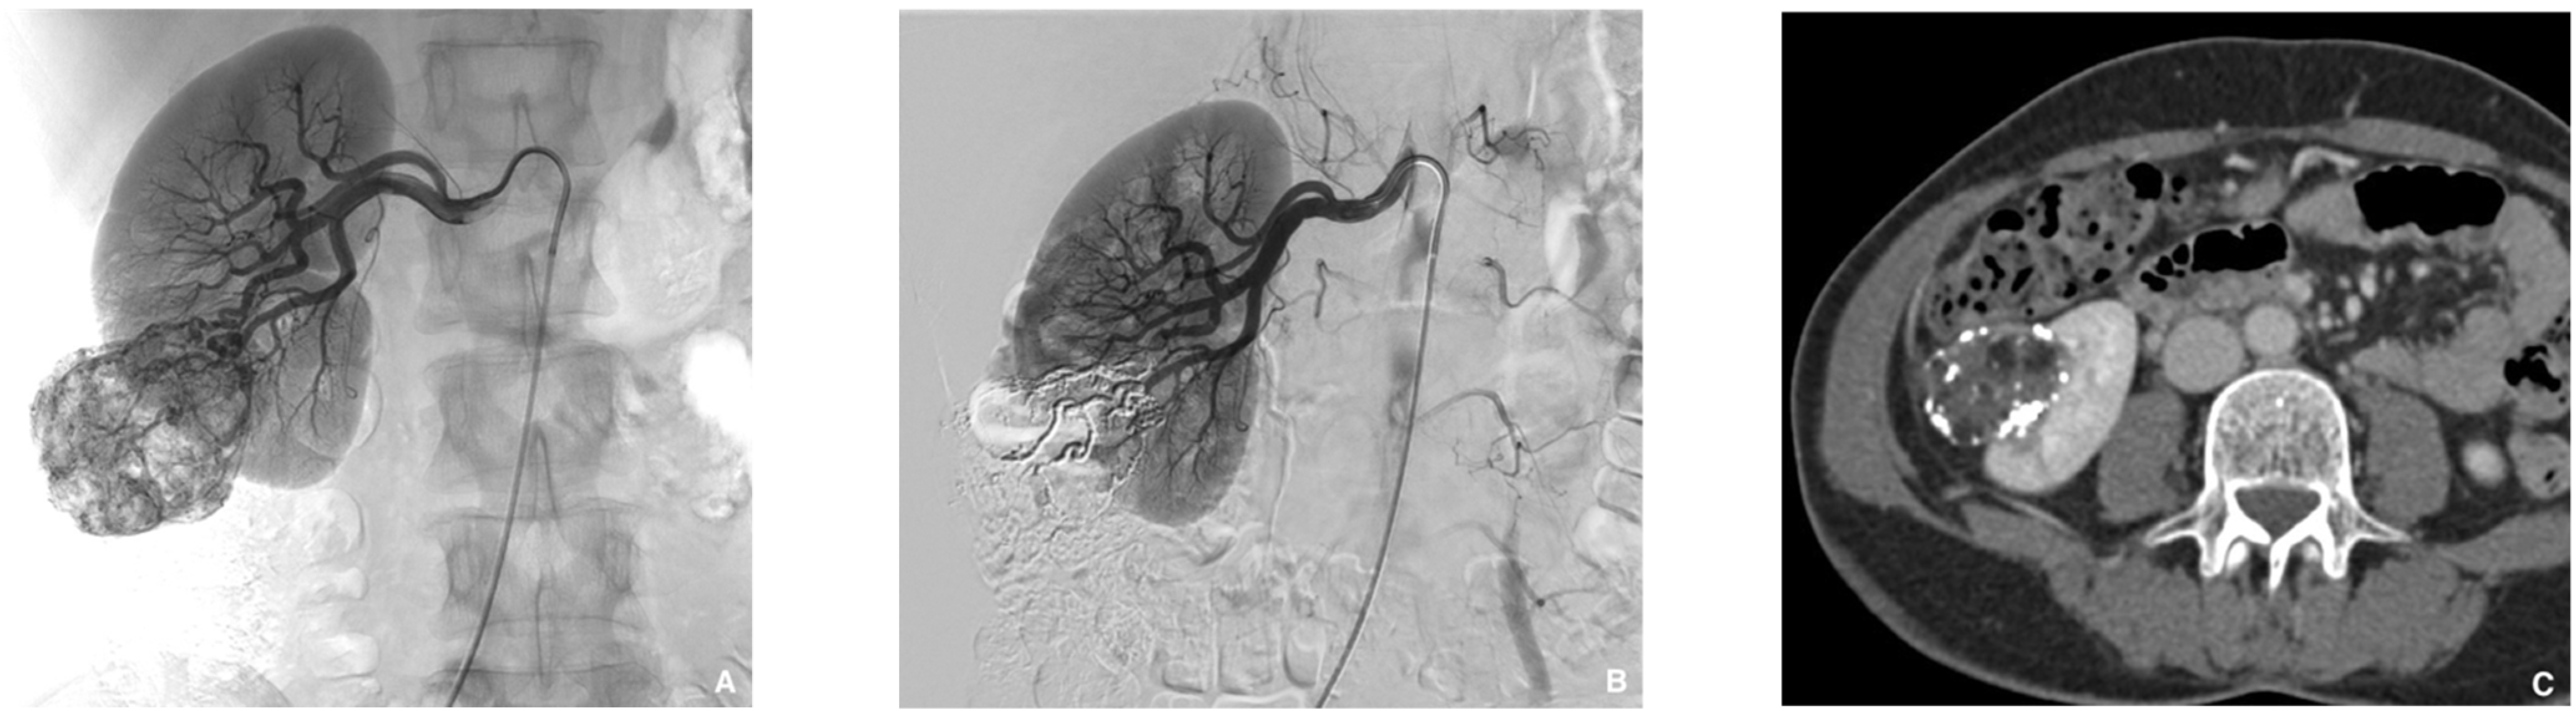

Figure 8. Typical left varicocele embolization with glue. (A) Left gonadal vein phlebography: a 5 French catheter is inserted in the left spermatic vein. A microcatheter is placed below the iliopectineal line and the dead space is filled with dextrose 5%, to avoid intracatheter glue polymerization. Embolization procedure is then performed using glue mixed with lipiodol at a ratio of 1:1 to get fast polymerization and avoid migration in case of reflux. Lipiodol–glue mixture is then injected under strict fluoroscopy, with continuous injection performed manually and a display of real-time distribution. The glue injection begins in the distal intrapelvic segment of the gonadal vein, and the catheter is withdrawn slowly while injecting NBCA under fluoroscopic control. Injection is then stopped before the pampiniform plexus is reached. The microcatheter is then removed when the glue fills the venous space selected beforehand. (B) Here we can see the cast of glue along the left spermatic vein after embolization.